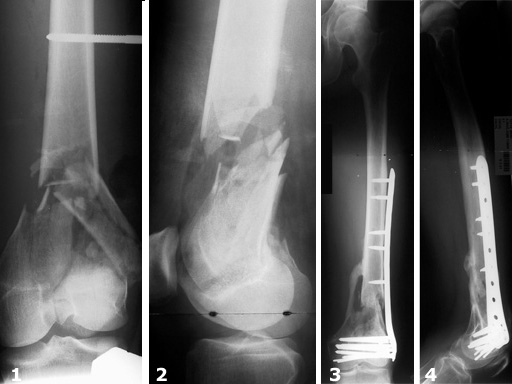

Female, 27 years

The LCP distal femur (DF) is indicated for distal shaft, supracondylar, intraarticular, and extraarticular, as well as periprosthetic fractures. Until recently, the plates were available in lengths up to 13 holes, with the longest plates 300 mm. Longer plates may be useful for appropriate bridging of comminuted fractures or for spanning a hip prosthesis to avoid stress risers in the proximal femur. For the treatment of these fracture types, additional plate lengths of 15, 17, and 19 holes with a maximum length of 436 mm are now available in left and right versions. They have the same design as the existing 513-hole plates and can be used with the same aiming arm, instruments, and screws.

From December 1996 to November 1998 116 fractures (112 patients) were treated with the new stabilization system as part of a prospective multicenter study. The follow-up period was 13.7 months on average. Principle clinical investigator was N. Haas, Berlin. The criteria for inclusion were distal femoral shaft fractures and supracondylar and intraarticular femoral fractures of all degrees of severity. In this study, thirty-one distal femoral shaft fractures and eighty-five supracondylar and/or intraarticular femoral fractures were treated. There was a total of 45% (n=52) complex intraarticular fractures. With reference to the fractures treated, the follow-up rate was 93%. In 90% of the cases treated and followed up, fracture consolidation during the observation period could be confirmed.